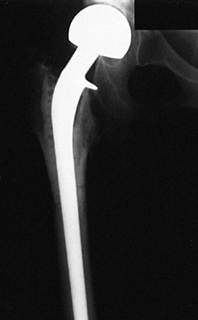

for replacement include the following: a large osteoarticular

allograft, a large diaphyseal allograft with a custom metallic joint

replacement threaded through the allograft, and a joint fusion using

sliding autografts with or without allograft bone. Preliminary evidence

suggests that diaphyseal allografts used in combination with joint

replacements are superior to large osteoarticular allografts for

replacement of large osteoarticular defects (10).

procedures. The more recent technique of threading a long-stem

customized joint replacement through a large diaphyseal allograft (10) appears to give better results, at least in the short term.

All of these grafts are best protected by screws, a porous fixed

acetabular component, a plate, or some combination of these items.

![]() |

|

Figure 9.15. A large acetabular allograft (B) for a low-grade fibrous histiocytoma (A) of the acetabulum is shown.